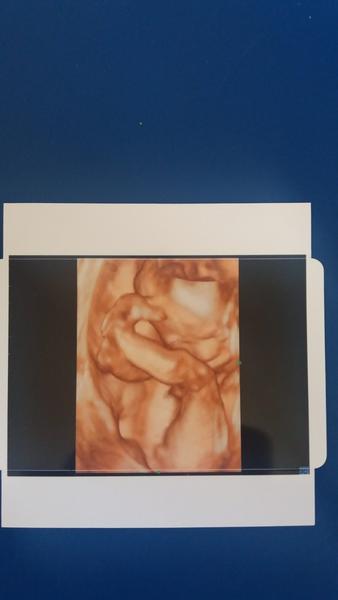

@jluciy přesně tak znám 😀 tady je náš pytlík 😀 pindíka má schovaného za pupeční šňůrou 😀